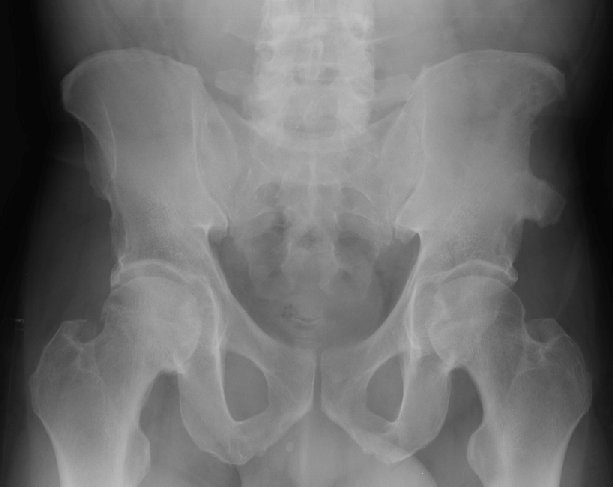

Return to Avulsion Fracture (Pelvis)